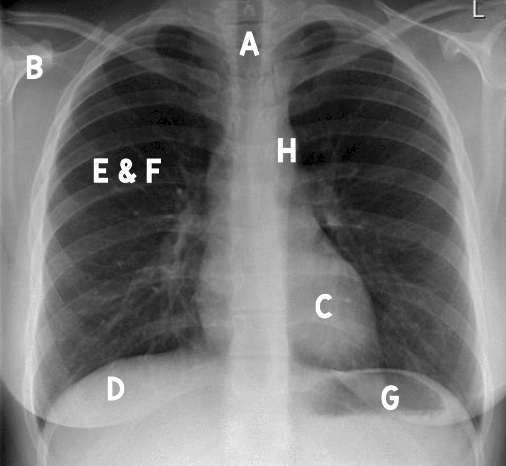

List A-I

(I is not Depicted)

A: Airway

B: Bone

C: Cardiac Silouette

D: Diaphragm

E & F: Equal Lung Fields

G: Gastric Bubble

H: Hilum (and Medastinum)

I: Invasive Lines (Not Shown)